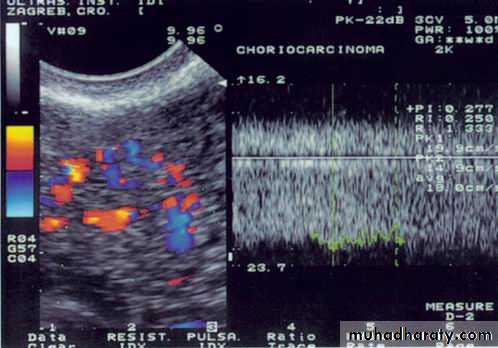

absence of chorionic villiDoppler image of choriocarcinoma

Doppler image of choriocarcinoma

Ultrasound and doppler examination